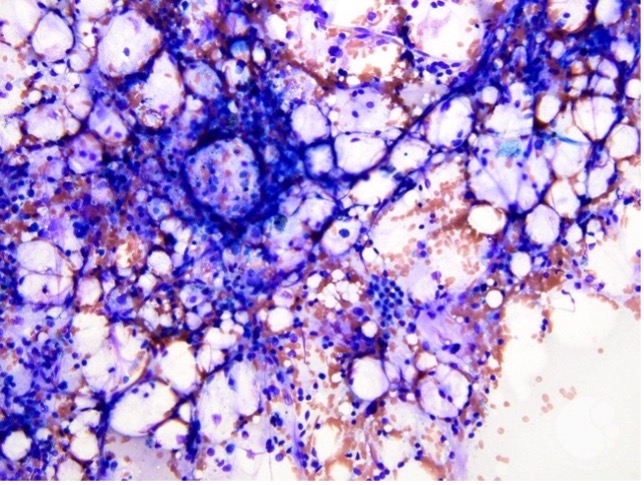

Investigations (additional)

Haematology